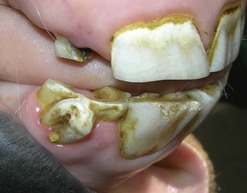

Fig. 8.5 (A) This young horse has developmental absence of 202, with mesial (medial) drifting of 203 into its site, with consequent overgrowth of the unopposed opposite 302, that is more obvious when the mouth is open (B). A diastema between 301 and 302 may be due to the overgrowth of 302 causing it to be laterally (distally) displaced.